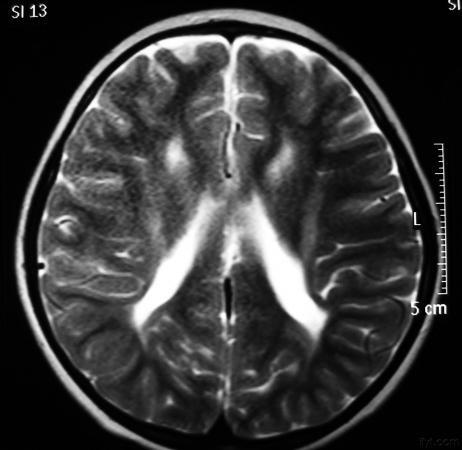

主要与脑缺血缺氧有关,多见于早产儿,是造成脑瘫的主要原因

影像学发生于侧脑室周围,侧脑室扩大,脑白质减少。扩大的侧脑室外缘常不规则为其特点,多为双侧脑室同时扩大。脑白质减少,脑皮层与脑室侧缘相近。MRI T1呈低信号,T2呈高信号。